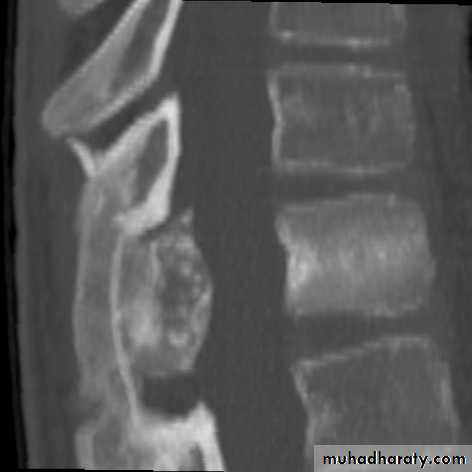

Osteoblastoma (giant osteoid osteoma)

It’s benign and similar to osteoid osteoma but its larger and more cellular.It occurs in young adults, males more than females.

Its commoner in the spine and flat bones& usually presents as pain or muscle spasm.X-ray shows well-defined lytic lesion surrounded by thin zone of sclerosis, it may contain flecks of calcification.

Treatment is by local excision and bone graft.

Always there is tendency for recurrence and malignant changes are reported.Bone cysts(tumor like conditions)